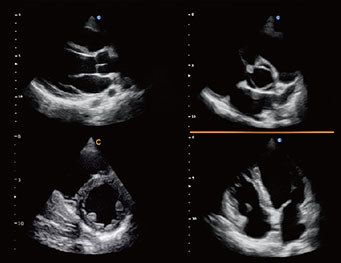

Cardiac, 4B Mode